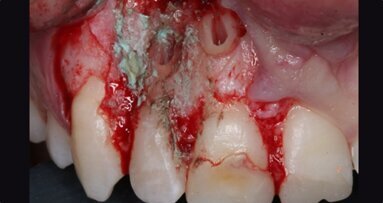

Upon this finding, the hemisection procedure was discussed with the patient, and he gave his full consent to perform it. Initially, the distal canal was gently irrigated with sodium hypochlorite at a 5% concentration and the canal medicated with calcium hydroxide (Fig. 3). At a second appointment 15 days later, the buccal abscess had receded (Fig. 4). The mesial root canal was then treated conventionally, determining the working length with an electronic apex locator (Root ZX II; Morita), performing instrumentation with nickel–titanium files (Pro-Flexi Files, Denco) and obturating with gutta-percha and a bioceramic sealer using the single-cone technique (CeraSeal, Meta Biomed). A resin core was placed with a dual-polymerising composite (CompCore AF, Premier Dental; Figs. 5 & 6).

Thereafter, the hemisection procedure was done under local anaesthesia (4% articaine with 1:100,000 adrenaline; Septodont). Under the microscope, an intra-sulcular incision was performed with a #15C blade, and a partial-thickness flap without vertical incisions was raised to observe the furcal area and resect the distal root and its coronal portion with a fissure diamond bur (Figs. 7–9). Curettage of the granulation tissue was performed and the area rinsed with saline, and a synthetic bone graft (DM Bone, Meta Biomed) was placed in the alveolar socket (Fig. 10). Posteriorly, the flap was repositioned and sutured with #6-0 polypropylene material. The sutures were removed seven days later, and the patient was followed up until three months later. At this point, the tissue had healed, and the definitive restoration procedure was initiated. The tooth remnant was prepared, and a fixed bridge with two cast metal extensions cemented on to previously prepared rests on the occlusal aspect of the neighbouring teeth was placed (Fig. 11).